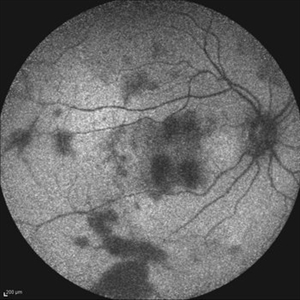

Acute Idiopathic Occlusive Retinal Vasculitis Acute Idiopathic Occlusive Retinal VasculitisMay 31 2014 by Hamid Ahmadieh, MD Wide- field fluorescein angiogram of the right eye of a 28-year-old woman with acute drop of vision due to occlusive retinal vasculitis leading to extensive capillary nonperfusion and macular infarction. Photographer: Naghmeh Nozhat, Negah Eye Center, Tehran Imaging device: Heidelberg Spectralis Condition/keywords: capillary nonperfusion, retinal infarction, retinal vasculitis

Acute Idiopathic Occlusive Retinal Vasculitis Acute Idiopathic Occlusive Retinal VasculitisMay 31 2014 by Hamid Ahmadieh, MD Mid phase fluorescein angiogram of the right eye of a 28-year-old woman with acute drop of vision due to occlusive retinal vasculitis leading to extensive capillary nonperfusion and macular infarction. Photographer: Naghmeh Nozhat, Negah Eye Center, Tehran Imaging device: Heidelberg Spectralis Condition/keywords: capillary nonperfusion, retinal vasculitis

Acute Idiopathic Occlusive Retinal Vasculitis Acute Idiopathic Occlusive Retinal VasculitisMay 31 2014 by Hamid Ahmadieh, MD Early phase fluorescein angiogram of the right eye of a 28-year-old woman with acute drop of vision due to occlusive retinal vasculitis leading to extensive capillary nonperfusion and macular infarction. Photographer: Naghmeh Nozhat, Negah Eye Center, Tehran Imaging device: Heidelberg Spectralis Condition/keywords: retinal vasculitis

Acute Idiopathic Occlusive Retinal Vasculitis Acute Idiopathic Occlusive Retinal VasculitisMay 31 2014 by Hamid Ahmadieh, MD Fundus autofluorescence image of the right eye of a 28-year-old woman with acute drop of vision due to occlusive retinal vasculitis leading to extensive nerve fiber layer infarction and retinal hemorrhages. Photographer: Naghmeh Nozhat, Negah Eye Center, Tehran Imaging device: Heidelberg Spectralis Condition/keywords: fundus autofluorescence (FAF), retinal vasculitis

Acute Idiopathic Occlusive Retinal Vasculitis Acute Idiopathic Occlusive Retinal VasculitisMay 31 2014 by Hamid Ahmadieh, MD Color fundus photograph of the right eye of a 28-year-old woman with sudden drop of vision due to acute occlusive retinal vasculitis leading to extensive nerve fiber layer infarction and retinal hemorrhages. Photographer: Naghmeh Nozhat, Negah Eye Center, Tehran Condition/keywords: color fundus photograph, cotton wool spots, retinal hemorrhage, retinal ischemia